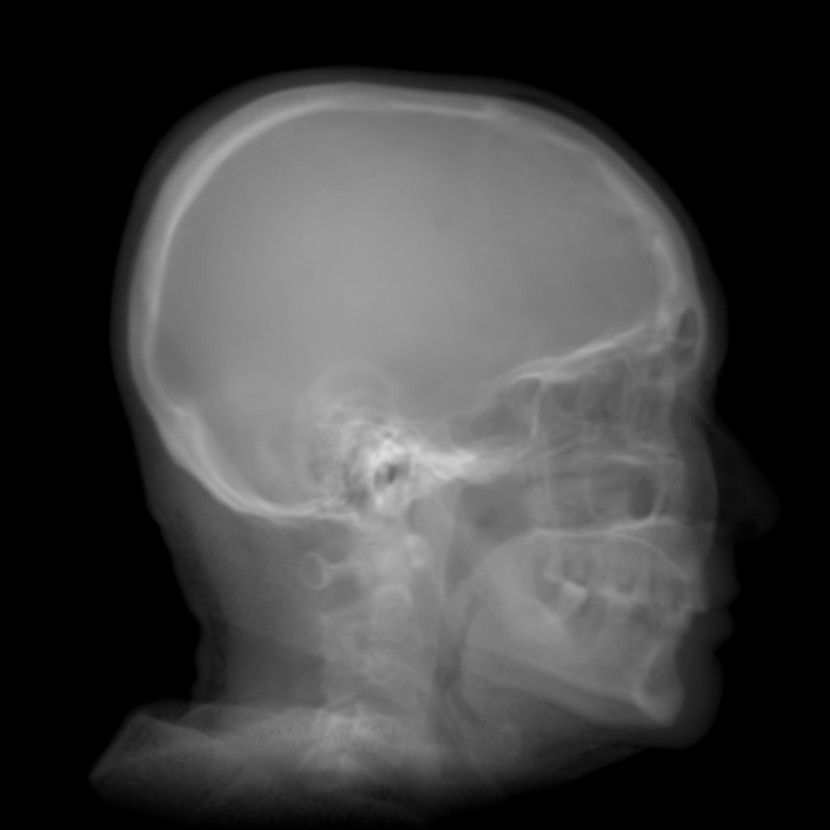

Refer to caption

(a) Real cephalogram

(b) Synthetic cephalogram

(c) Plot of samples and sigmoid curves

Fig. 2: Image contrast difference between real conventional cephalograms and RayCast synthetic cephalograms: (a) a real cephalogram example; (b) a RayCast synthetic cephalogram example; (c) the plot of samples between RayCast synthetic cephalograms and real cephalograms with an original sigmoid curve (red) and our proposed modified sigmoid curve (blue).

In Fig. 2, one real conventional cephalogram example and one example of 𝒈𝒈\boldsymbol{g} are displayed, where evident image contrast difference between these two images is observed. It is because the X-ray films used in conventional cephalograms have the special nonlinear optical property that the characteristic curve between optical density and logarithmized X-ray exposure has a sigmoid-like shape [42]. According to the Lambert-Beer law, the logarithmized X-ray exposure is equivalent to the attenuation integral. It indicates that the intensity relation between the desired cephalogram and the attenuation integral image 𝒈𝒈\boldsymbol{g} should also exhibit a sigmoid-like curve. Therefore, to make the image contrast of synthetic cephalograms similar to conventional cephalograms, a sigmoid intensity transform is necessary.

To find the parameters for the above general sigmoid transform, the mean intensity values of samples chosen in certain regions of 𝒈𝒈\boldsymbol{g} together with the corresponding values sampled from real conventional cephalograms are plotted as black dots in Fig. 2(c). The sigmoid transform of Eqn. (4) is plotted as the red-dotted curve, whose parameters are determined by least squares curve fitting. As displayed, most samples are located near the sigmoid curve, which is consistent with the characteristic curve in X-ray films. Note that the positions of the samples are approximated very coarsely due to the absence of dental CBCT volumes and their corresponding cephalograms. With matching pairs, a more accurate intensity transform can be learned.

where the intensity transform is a modified sigmoid function, illustrated as the blue-dotted curve in Fig. 2.